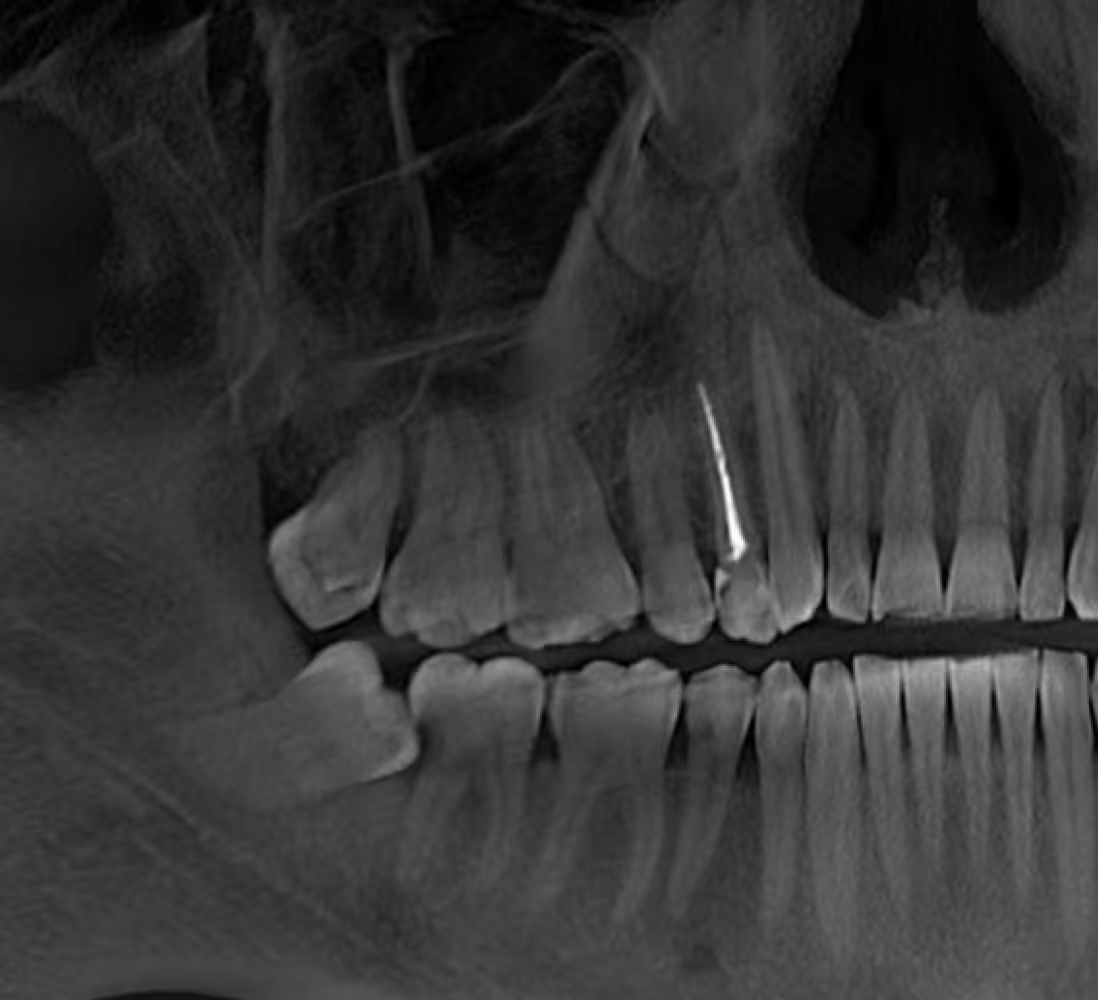

Вартість залежить від складності випадку та кількості каналів у зубі. Остаточну вартість визначає лікар після огляду або КТ. У більшості випадків лікування починається під час першого візиту.

У нашій клініці проводиться невідкладна стоматологічна допомога: лікування каналів зуба, термінове видалення зубів та відновлення сколів. Ми приймаємо пацієнтів у день звернення, проводимо діагностику на місці та швидко усуваємо причину болю.